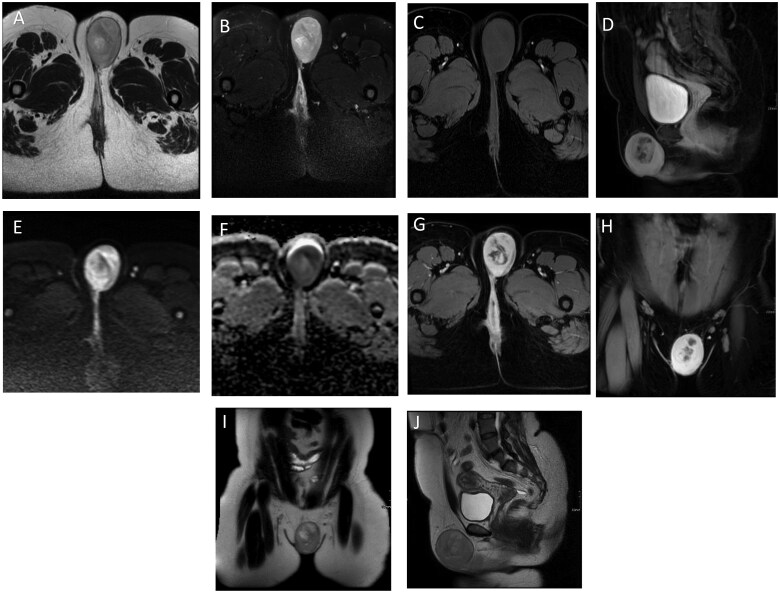

Vulvar dermatofibrosarcoma protuberans (DFSP) is a rare pathology. So far, only limited number of cases have been reported in literature. In the present case, we discuss a 38-year-old female presented with a painful left vulvar mass. She had a prior history of a left vulvar mass excision which was histopathologically confirmed as benign spindle cell epithelioma. The current mass, extending from the left labia majora to the left gluteal fold, was assessed via contrast-enhanced magnetic resonance imaging (MRI), revealing a well-defined, lobulated lesion with proximity to the distal urethra and clitoris without definite invasion. The patient underwent a wide local excision, radical vulvectomy, and left inguinofemoral lymphadenectomy. Postoperatively, she experienced fever, vulvar swelling, and dysuria. Follow-up MRI demonstrated total resolution of the vulvar mass and collection with no recurrence. Histopathology identified the mass as DFSP, with all surgical margins negative.